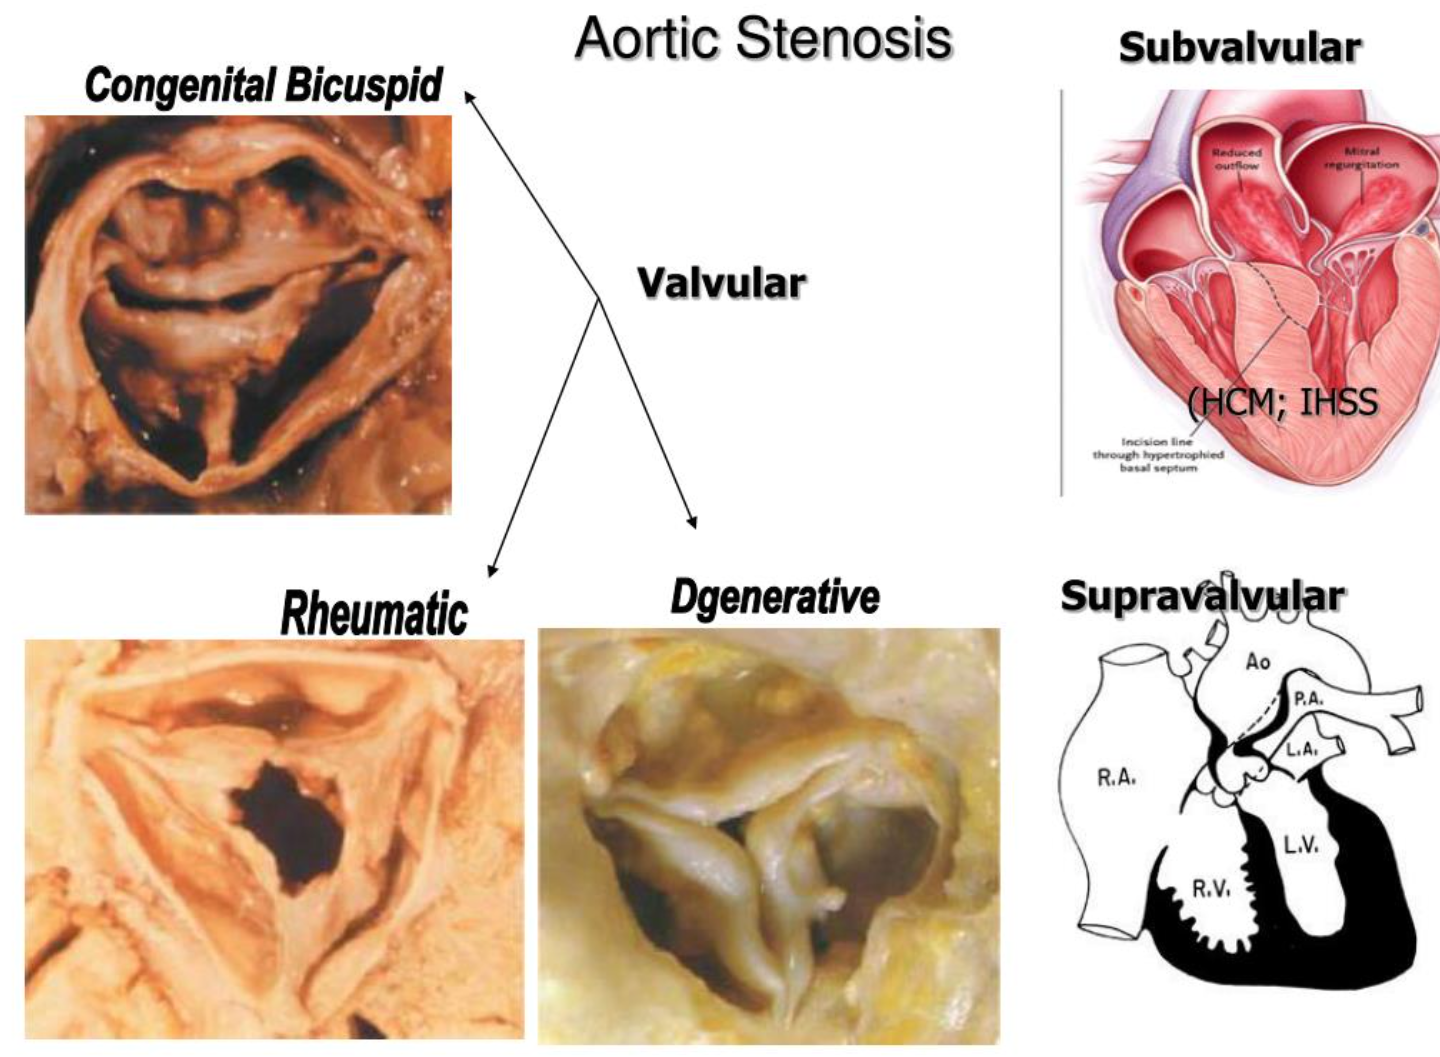

Types:

- Supravalvular: Williams Syndrome AD

- Subvalvular

- Valvular

Etiology

- Aortic valve sclerosis: C st. Normal tips. ↑ with age ~ atherosclerosis

- Bicuspid aortic valve (BAV): Fusion leaflets in utero. C: males (3:1). Dystrophic calcification and degeneration. Associated with A coarctation, root dilation & A dissection. Symptoms of AS: earlier than in regular aortic valve calcification.

- Rheumatic fever: C in lower-income countries. Stenosis is caused by commissural fusion. 2nd turbulent flow, calcification of tips.